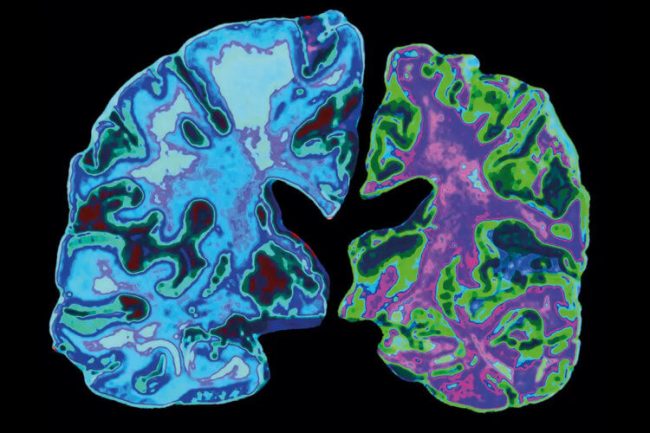

Изменения белковой структуры в крови могут сигнализировать о болезни Альцгеймера

По оценкам Ассоциации Альцгеймера, болезнь Альцгеймера поражает около 7,2 миллиона американцев в возрасте 65 лет и старше. Современные тесты часто измеряют уровни двух белков — бета-амилоида (A?) и фосфорилированного тау-белка (p-tau) — в крови или спинномозговой жидкости, но эти маркеры могут не в полной мере отражать более ранние биологические изменения, связанные с прогрессированием заболевания. Ученые…